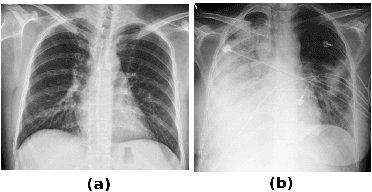

Pulmonary opacification is the inflammation in the lungs caused by many respiratory ailments, including the novel corona virus disease 2019 (COVID-19). Chest X-rays (CXRs) with such opacifications render regions of lungs imperceptible, making it difficult to perform automated image analysis on them. In this work, we focus on segmenting lungs from such abnormal CXRs as part of a pipeline aimed at automated risk scoring of COVID-19 from CXRs. We treat the high opacity regions as missing data and present a modified CNN-based image segmentation network that utilizes a deep generative model for data imputation. We train this model on normal CXRs with extensive data augmentation and demonstrate the usefulness of this model to extend to cases with extreme abnormalities.